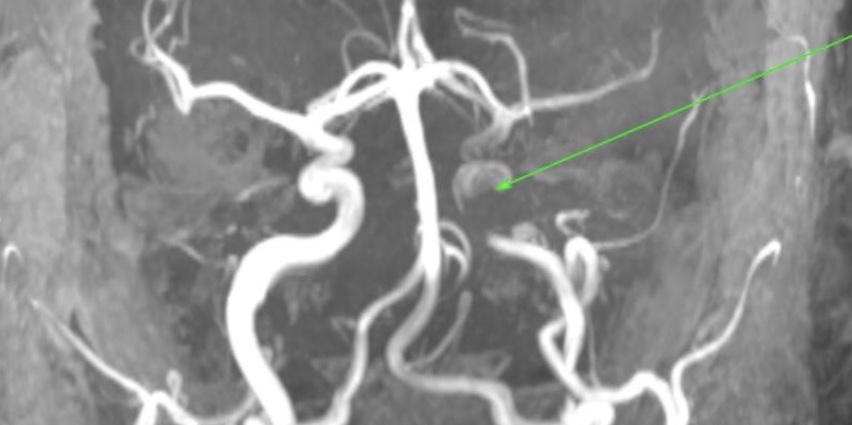

Computed tomography (CT) brain was normal. Magnetic resonance imaging (MRI) brain, magnetic resonance angiography (MRA) brain and MRA both carotids were subsequently undertaken and revealed a left internal carotid artery dissection (Figure 1) with no evidence of cerebral infarction or haemorrhage. A subsequent ultrasound Doppler of the carotid arteries characterised the lesion to be at least 2.2cm of the distal left internal carotid artery.